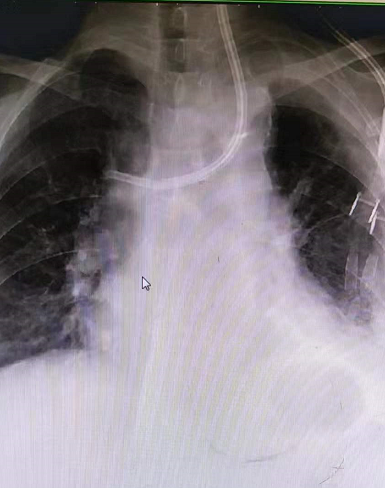

王女士,确诊尿毒症7+年时间,长期依靠左侧cuff导管行血液透析治疗,因确诊导管感染,经过反复治疗后效果不佳,所以必须拔除维持患者生命的唯一的血管通路,但是血管通路是尿毒症患者维持生存的必备条件,目前患者又处于病危状态、高钾、水负荷重,心衰明显,必须立即建立新的血管通路行血液透析治疗去维持生命,由于患者自身血管条件差,动静脉内瘘建立困难,临时血管通路建立难度极大,临时安置股静脉导管、颈内静脉导管均失败,不能满足血液透析要求,对此,患者悲痛欲绝、陷入绝望,家属也不放弃任何能够救治的机会,啃啃哀求郑医生能够为患者开辟一条“活路”;于是肾病科主任毕伟红、副主任王婷立刻紧急召开血管通路小组会议,由于王女士基础疾病多且复杂,DSA下造影显示左侧头臂静脉重度狭窄伴血栓形成,手术难度及风险极大,经过讨论,主刀医生郑星和张艳玲医生快速为患者量身定制手术方案,决定联合运用介入技术(DSA)+PTA技术,为王女士开辟一条新的“活路”。王女士,确诊尿毒症7+年时间,长期依靠左侧cuff导管行血液透析治疗,因确诊导管感染,经过反复治疗后效果不佳,所以必须拔除维持患者生命的唯一的血管通路,但是血管通路是尿毒症患者维持生存的必备条件,目前患者又处于病危状态、高钾、水负荷重,心衰明显,必须立即建立新的血管通路行血液透析治疗去维持生命,由于患者自身血管条件差,动静脉内瘘建立困难,临时血管通路建立难度极大,临时安置股静脉导管、颈内静脉导管均失败,不能满足血液透析要求,对此,患者悲痛欲绝、陷入绝望,家属也不放弃任何能够救治的机会,啃啃哀求郑医生能够为患者开辟一条“活路”;于是肾病科主任毕伟红、副主任王婷立刻紧急召开血管通路小组会议,由于王女士基础疾病多且复杂,DSA下造影显示左侧头臂静脉重度狭窄伴血栓形成,手术难度及风险极大,经过讨论,主刀医生郑星和张艳玲医生快速为患者量身定制手术方案,决定联合运用介入技术(DSA)+PTA技术,为王女士开辟一条新的“活路”。王女士,确诊尿毒症7+年时间,长期依靠左侧cuff导管行血液透析治疗,因确诊导管感染,经过反复治疗后效果不佳,所以必须拔除维持患者生命的唯一的血管通路,但是血管通路是尿毒症患者维持生存的必备条件,目前患者又处于病危状态、高钾、水负荷重,心衰明显,必须立即建立新的血管通路行血液透析治疗去维持生命,由于患者自身血管条件差,动静脉内瘘建立困难,临时血管通路建立难度极大,临时安置股静脉导管、颈内静脉导管均失败,不能满足血液透析要求,对此,患者悲痛欲绝、陷入绝望,家属也不放弃任何能够救治的机会,啃啃哀求郑医生能够为患者开辟一条“活路”;于是肾病科主任毕伟红、副主任王婷立刻紧急召开血管通路小组会议,由于王女士基础疾病多且复杂,DSA下造影显示左侧头臂静脉重度狭窄伴血栓形成,手术难度及风险极大,经过讨论,主刀医生郑星和张艳玲医生快速为患者量身定制手术方案,决定联合运用介入技术(DSA)+PTA技术,为王女士开辟一条新的“活路”。郑星医生表示在:介入技术能够快速发现患者血管通路问题所在,能让“隐形”的血管可视化,精准定位,提高手术操作成功率;由于王女士左侧头臂静脉重度狭窄伴血栓形成,导管通过狭窄部位困难,然而利用PTA技术能够扩张血管重度狭窄部位,让导管顺利通过,两种技术联合运用,极大地降低手术风险,减少了患者的痛苦。生命线的顺利重置,血液透析治疗的顺利开展,让患者及家属顿时喜笑颜开,重燃了患者生存的希望。

(术前) (术前) (术后)

介入技术(DSA):指通过在血管中注入造影剂,使血管显影,根据血管的分布、形态、位置等变化来判断病变的具体部位、范围及程度,并可经导管行介入治疗。

经皮血管腔内血管成形术(PTA):通过经皮穿刺血管,置入导丝,沿导丝将球囊输送至血管狭窄病变处,将扩张球囊送入血管狭窄部位并对其进行扩张,从而将狭窄血管矫正至正常血管内径。